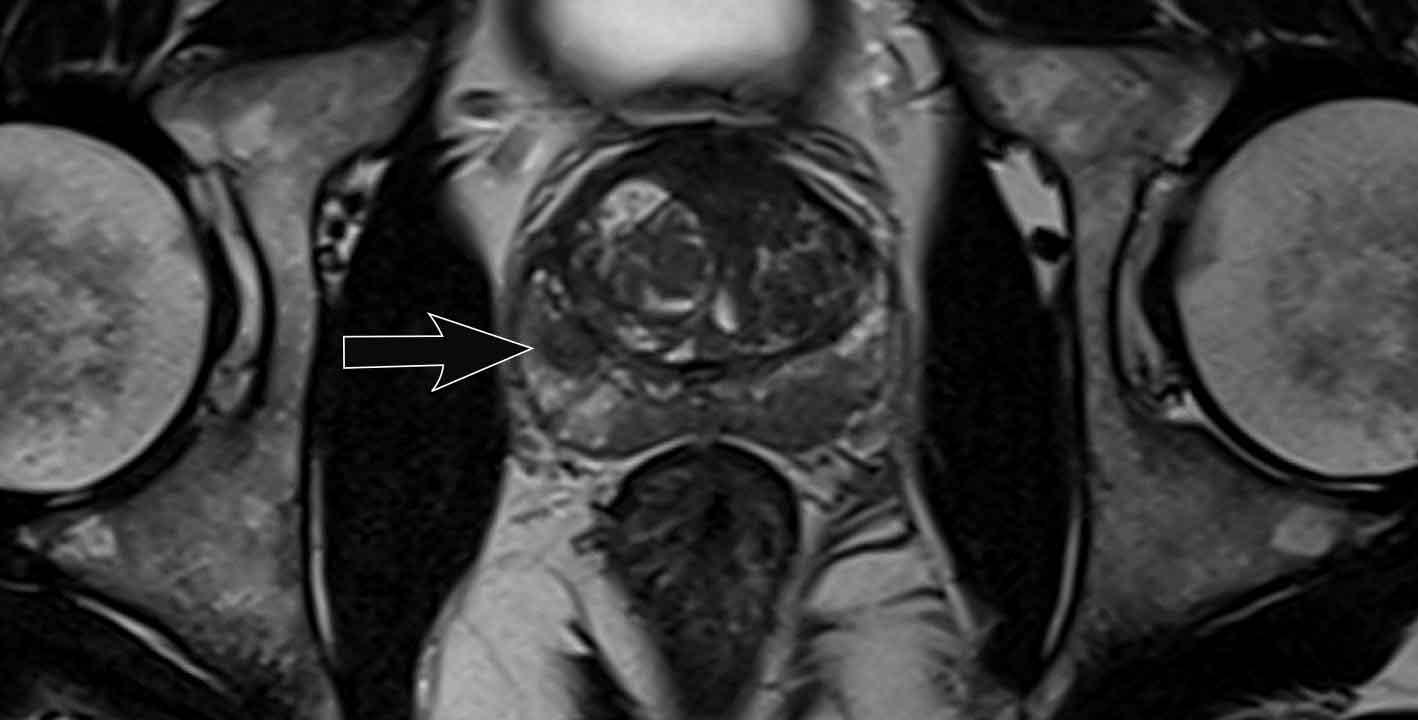

Các phát hiện bao gồm:

- Một tổn thương kích thước 17 mm (không hiển thị phép đo) nằm ở vùng ngoại vi, phía sau bên trái của phần giữa tuyến tiền liệt.

- Giảm tín hiệu rõ rệt trên ADC và tăng tín hiệu rõ rệt trên DWI.

- Tương ứng với vùng giảm tín hiệu trên chuỗi xung T2W.

- Trên chuỗi xung T2W, tổn thương tiếp xúc diện rộng với vỏ bao tuyến tiền liệt.

Tổn thương này được xếp vào phân loại PI-RADS 5 với nghi ngờ xâm lấn ra ngoài tuyến tiền liệt.

Điểm Gleason là 4+3.

Tổn thương nghi ngờ này có hạn chế khuếch tán đáng kể.

Giá trị ADC đo được là 440 mm²/s.

Giá trị ADC thấp cho thấy nguy cơ ác tính cao hơn.

Giá trị ADC thực tế có tương quan nghịch với khả năng ác tính có ý nghĩa lâm sàng.

Các giá trị trên 900 mm²/s được coi là có khả năng lành tính và dưới 750 mm²/s có khả năng ác tính.

Tuy nhiên, kết quả định lượng có thể khác nhau đáng kể giữa các máy chụp và các giao thức chụp.